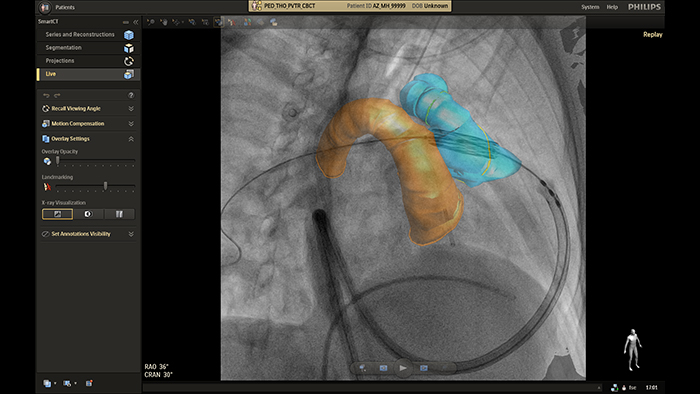

SmartCT live guidance